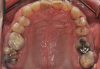

Fig 5. Pretreatment occlusal views: maxilla (Fig 5) and mandible (Fig 6).

Figure 5

Periodontal examination revealed generalized BOP and PDs up to 9 mm in the maxillary and mandibular molars with multiple furcations in each molar (Figure 2 through Figure 7). He presented with class I mobility in many posterior teeth and class II mobility in teeth Nos. 3 and 9 (maxillary right first molar and maxillary left central incisor, respectively). The periodontist decided to score tooth No. 3 for the PRS, as this was the most periodontally involved molar that was planned to be treated and maintained (Figure 2 and Figure 8). This tooth (maxillary right first molar = score 1) presented with probing depths of 7 mm (score 1); three total furcation invasions (score 3) (mesial [degree II furcation], buccal [degree I furcation], and distal [degree II furcation]); and a class II mobility (score 2). The total PRS for tooth No. 3 was 8, representing a "guarded" prognosis. Based on this score, the likelihood of not losing any teeth to periodontal disease for 15 years was 81%, and for 30 years the likelihood was just 56% (Figure 9).7